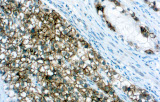

Integración en la oncología moderna guiada por biomarcadores

La literatura reciente destaca el papel creciente de la IHQ como sustituto del perfilado molecular y el descubrimiento de biomarcadores, particularmente en la subtipificación del cáncer de vejiga y próstata.